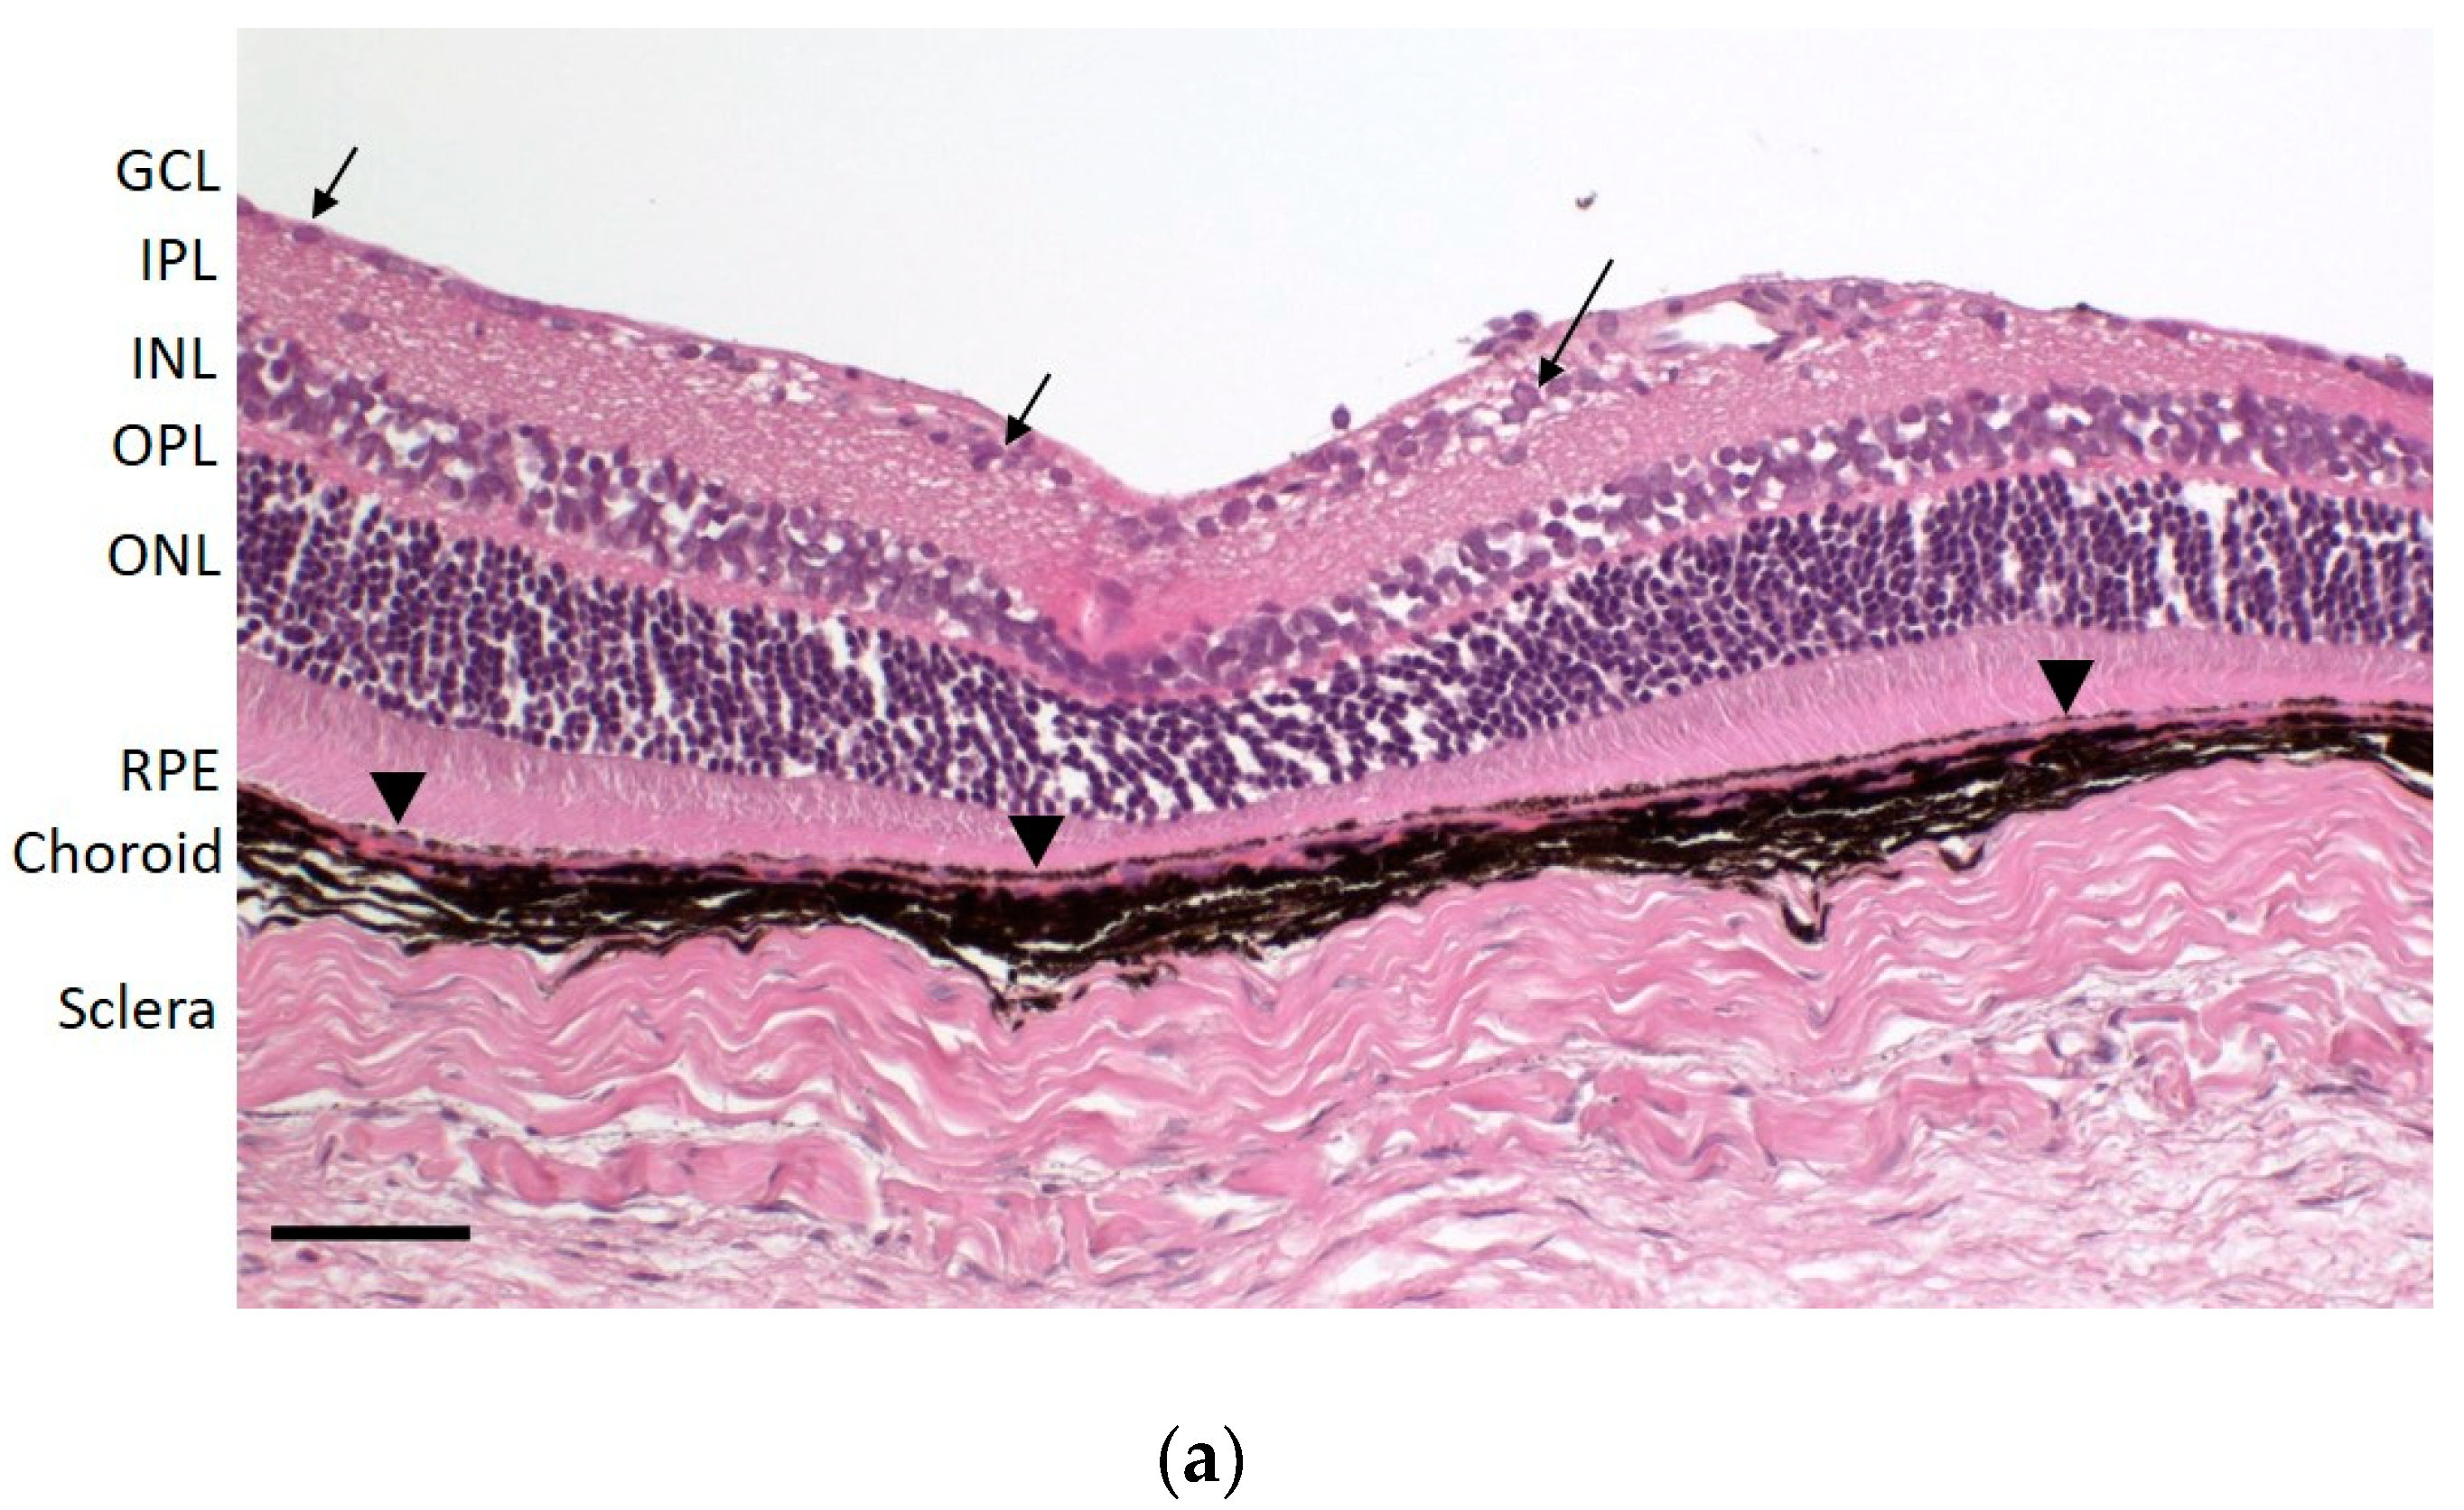

2.8. Histology

To investigate the level of cross-tissue contamination, we prepared the ocular tissues for histological examination using the above-described protocol. After separation of the different ocular layers, the tissues were cut into smaller pieces and transferred into histology cassettes. To avoid sample loss and to keep the samples flat, sponges and filter paper were used. The samples were fixed in 10% neutral buffered formalin for approximately 24 h, processed with an automated tissue processor (Tissue-Tek® VIP® 6, Sakura Finetek Europe B.V., Alphen aan den Rifn, the Netherlands), embedded in paraffin and cut in 3 µm sections. Staining with hematoxylin and eosin (HE) was performed according to standard protocols.

Small molecules exhibit high melanin binding potential, stressing the need for clean separation of the posterior segment tissues, retina and RPE-choroid, since a small contamination of the retina with melanin containing tissue could lead to a considerable over-estimation of retinal drug concentrations. Unfortunately, retina and RPE-choroid of the rat eye are very difficult to distinctly separate from one another. We chose to fix the eye in formalin before the separation process, as formalin is known to induce retinal detachment [

24] and preserve tissue structure. A short fixation time of 90 min, considerably shorter than the generally used tissue fixation times for histology purposes (overnight or longer), was optimal for our purpose.

Due to the massive concentration differences possible between pigmented and non-pigmented ocular tissues, we applied two methods to investigate retina contaminations with pigmented tissue. While the low melanin content determined in the pooled retinas via the less sensitive photometry was encouraging, the histology of the separated retinas demonstrated the efficiency of the separation process leading to essentially no contaminations with RPE-choroid. We consider this achievement of high importance for an accurate quantification of compounds with melanin binding potential in the retinal tissue.